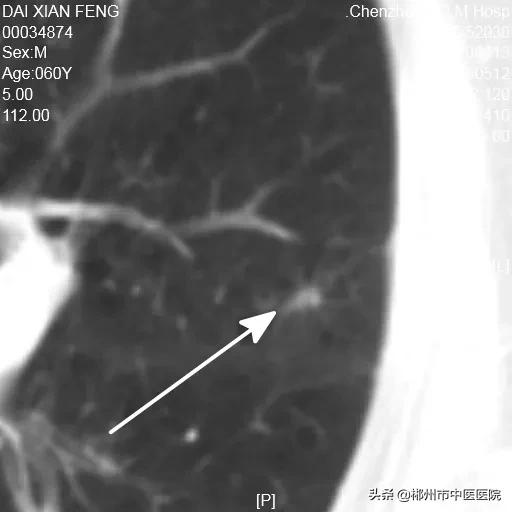

陀螺刀治疗前病灶大小15.3X12.4mm

第一次复查残留区域7X6mm

第二次复查残留区域5X3.4mm